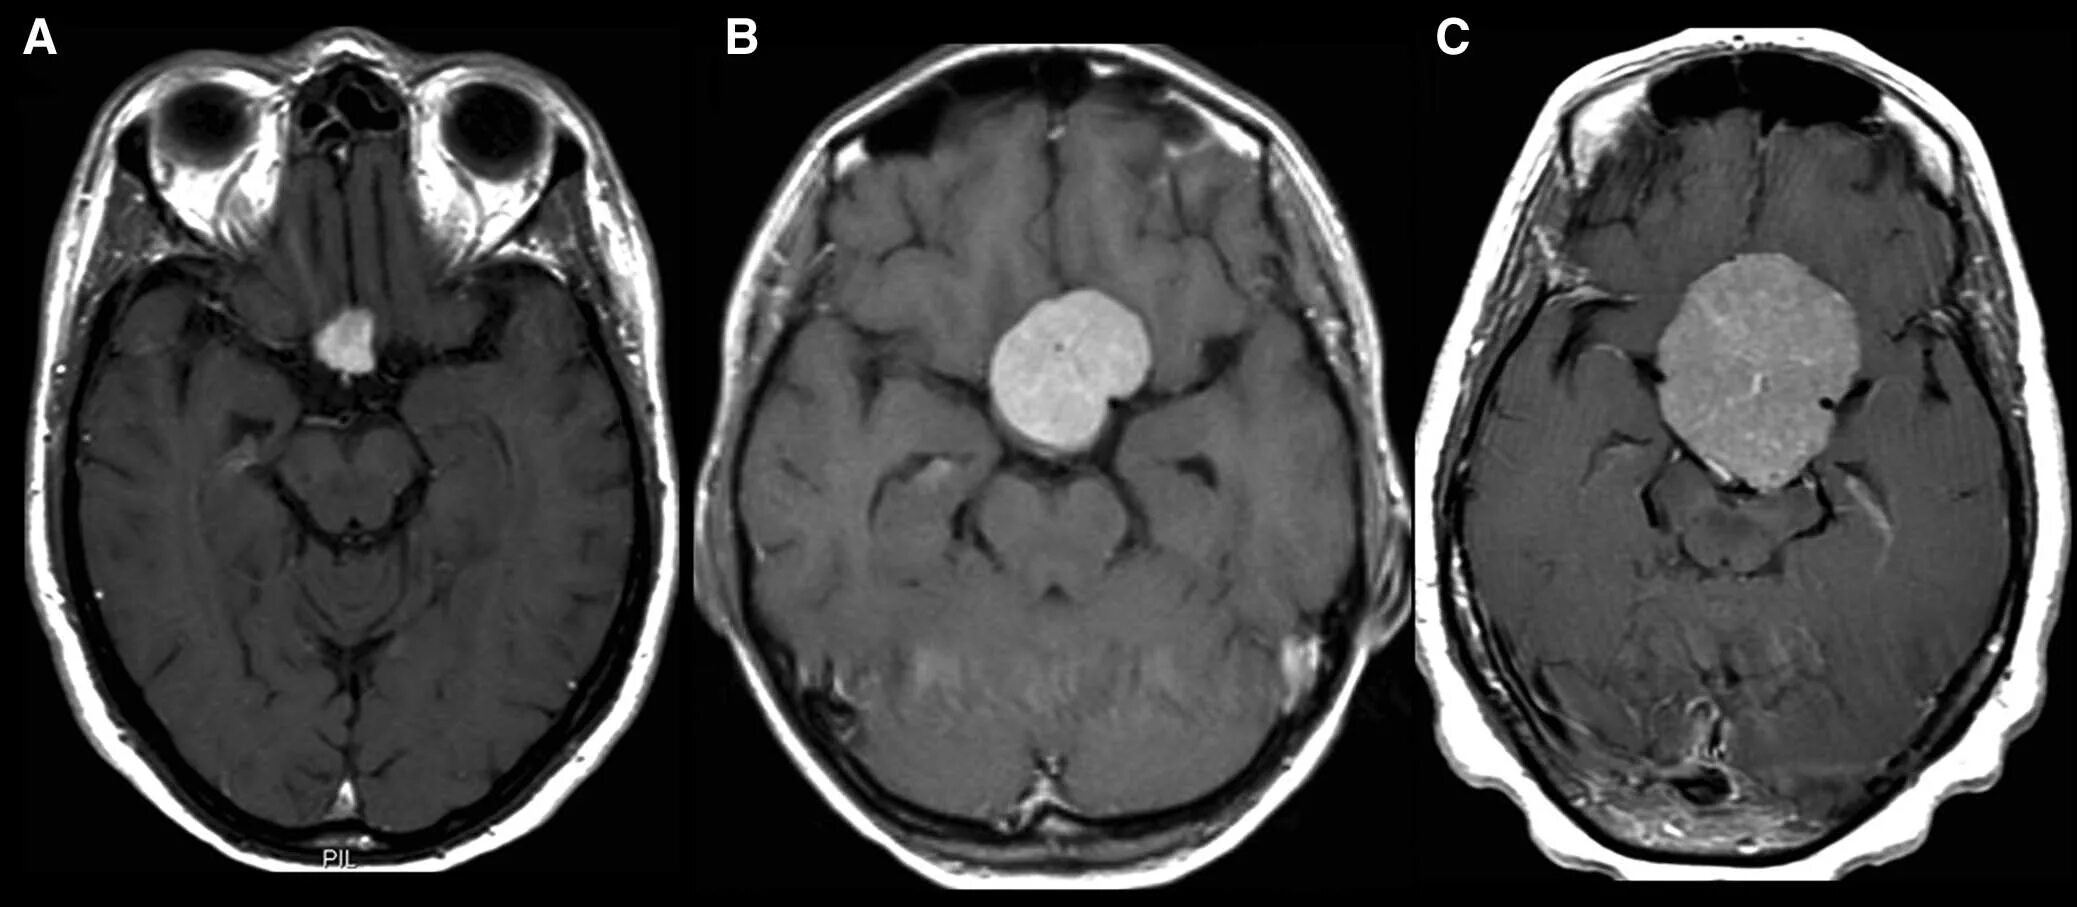

Опухоль головного мозга стадии. Опухоль головного мозга симптомы. Проявление опухоли головного мозга. Степени опухолей головного мозга. Методы исследования при опухоли головного мозга. Дополнительные методы исследования опухолей головного мозга. Диагноз кт с опухолью головного мозга. Дополнительные методы исследования при опухолях головного мозга.

Методы исследования при опухоли головного мозга. Дополнительные методы исследования опухолей головного мозга. Диагноз кт с опухолью головного мозга. Дополнительные методы исследования при опухолях головного мозга. Диагностика ра а желудка. РВК желудка дипгностика. Иагностика рада желудка. Методы диагностики в онкологии.

Диагностика ра а желудка. РВК желудка дипгностика. Иагностика рада желудка. Методы диагностики в онкологии. Опкхолльлголовного мозга. Новообразование в головном мозге. Злокачественная опухоль головного мозга.

Опкхолльлголовного мозга. Новообразование в головном мозге. Злокачественная опухоль головного мозга. Методы диагностики опухолей. Метод диагностики опухолей. Методы выявления опухоли. Этапы диагностики опухолей.

Маммография молочных желез объемное образование. Опухоль молочной железы. Онкология молочной железы. Опухольмолочныйжелезы. Доброкачественная злокачественная опухоль головного мозга мрт. Глиома головного мозга мрт. Опухоль головного мозга на кт.

Доброкачественная злокачественная опухоль головного мозга мрт. Глиома головного мозга мрт. Опухоль головного мозга на кт. Карциноид червеобразного отростка гистология. Карциноид кишечника гистология. Карциноид червеобразного отростка патанатомия. Карциноидная опухоль микропрепарат.

Карциноид червеобразного отростка гистология. Карциноид кишечника гистология. Карциноид червеобразного отростка патанатомия. Карциноидная опухоль микропрепарат. Мрт головного мозга с контрастированием. Мрт с контрастированием опухоль. Мрт головы с контрастом. Магнитно резонансная томография с контрастом головного мозга.

Мрт головного мозга с контрастированием. Мрт с контрастированием опухоль. Мрт головы с контрастом. Магнитно резонансная томография с контрастом головного мозга. Классификация опухолей. Классификация новообразований. Классификация опухолей по воз. Классификация воз опухолей костей.

Диагностические критерии глиомы головного мозга. Объемное образование головного мозга. Локализация опухолей головного мозга. Первичные и вторичные опухоли головного мозга.

Доброкачественная опухоль кости классификация. Классификация опухолей и опухолеподобных поражений костей. Классификация опухолей воз. Опухолеподобные заболевания костей. Глиобластома головного мозга мрт. Менингиома головного мозга мрт. Менингиома грейд. Опухоли мозга (менингиома);.

Глиобластома головного мозга мрт. Менингиома головного мозга мрт. Менингиома грейд. Опухоли мозга (менингиома);.